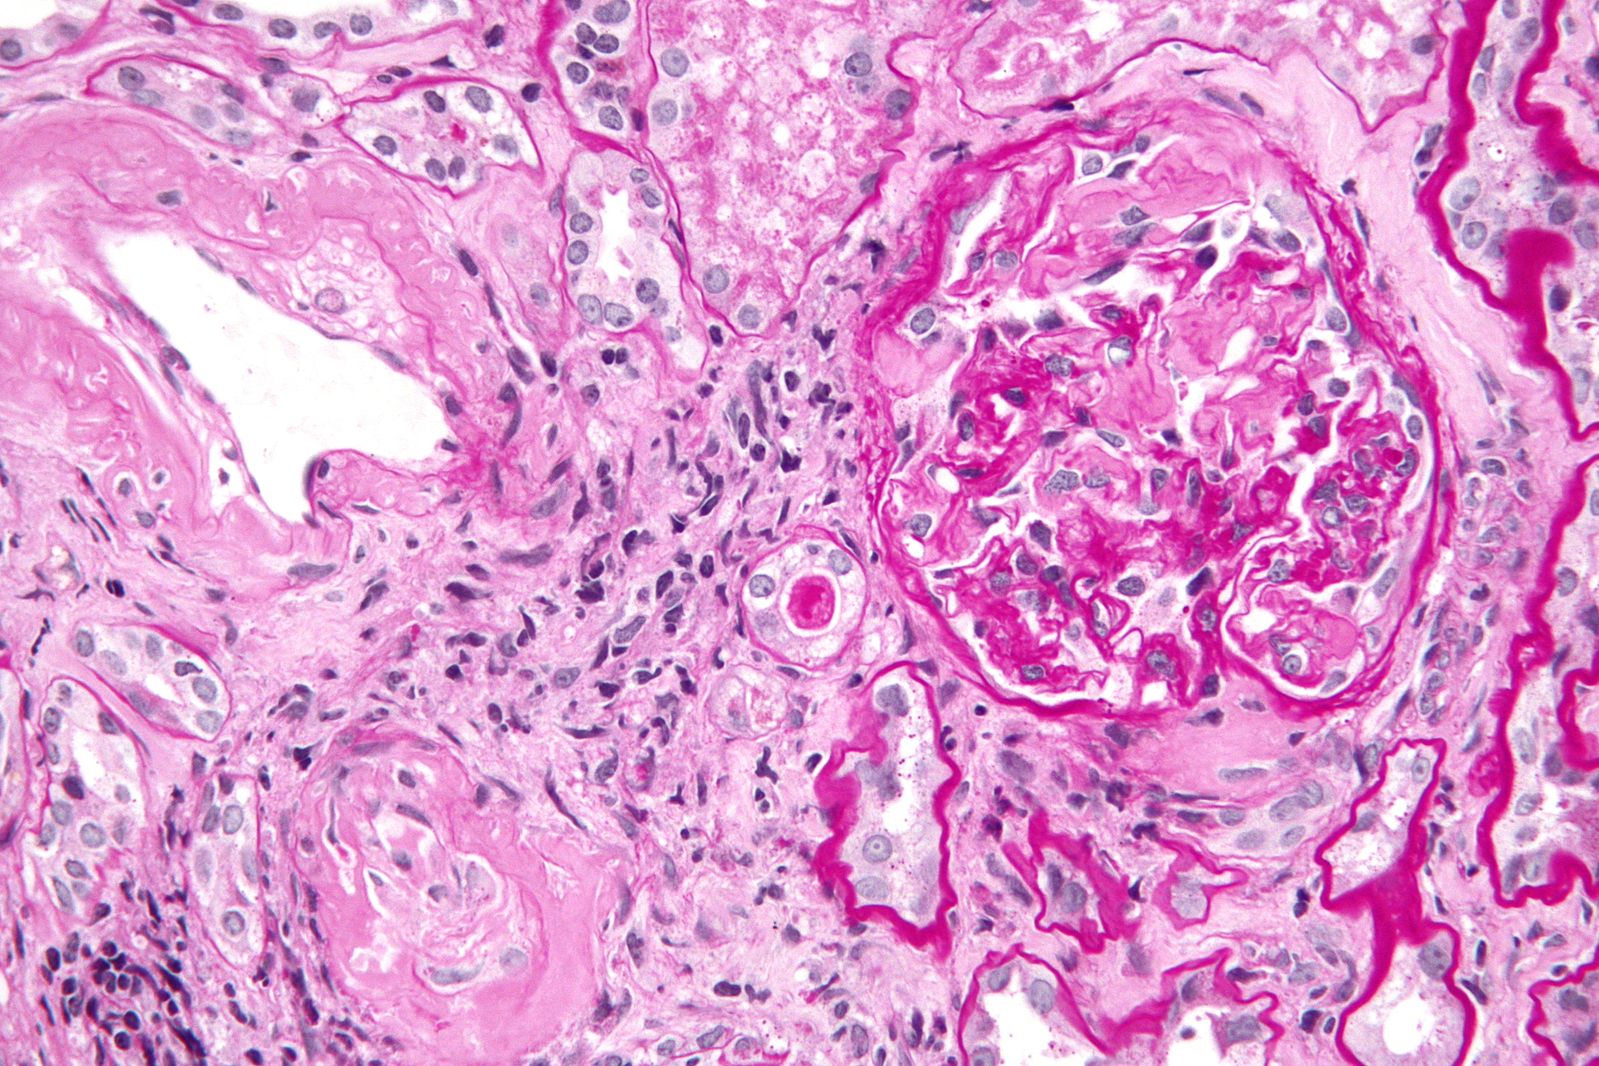

The diagnosis of amyloidosis is made by looking for amyloid fibrils. These fibrils can be seen in tissues removed from organs by a biopsy. The amyloid deposits give a specific birefringence when stained with congo red dye. Immunohistochemistry and immunofluorescence methods have to be used if the exact type of amyloid that is being deposited, is to be determined.

Amyloidosis is the condition in which there is an accumulation of an unusual protein in the tissues of the body.